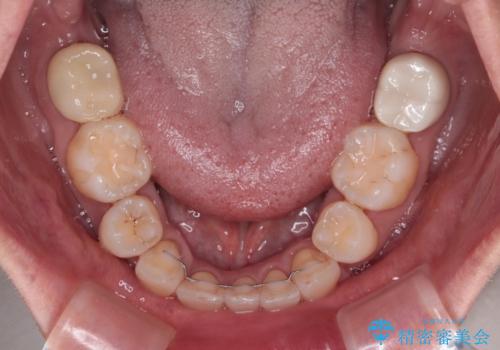

当初目論見通り、左右奥歯の咬み合わせはしっかりとさせることができました。

下唇に跡がつくほど飛び出していた上顎前歯も引っ込み、満足のいく仕上がりとなりました。